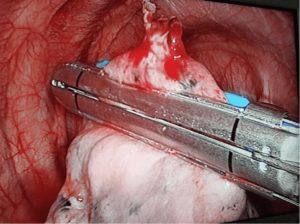

إذا كان الاستراحة الهوائي متكرر على نفس الجهة أو على الجهة الأخرى او إذا لم ينجح تركيب الأنبوب الصدرية في حل المشكلة وكان هناك تسريب للهواء اكثر من خمس ايام نضطر لإجراء جراحة عن طريق المنظار الصدري الجراحي لإغلاق منفذ تسريب الهواء مع ازالة تجويف الغشاء البلوري لضمان عدم حدوث الألواح الهوائية مرةأخرى، وهي عملية بسيطة تستغرق من 60 إلى 90 دقيقة.

وهي تختلف تماما عن عملية تقشير الغشاء البلوري